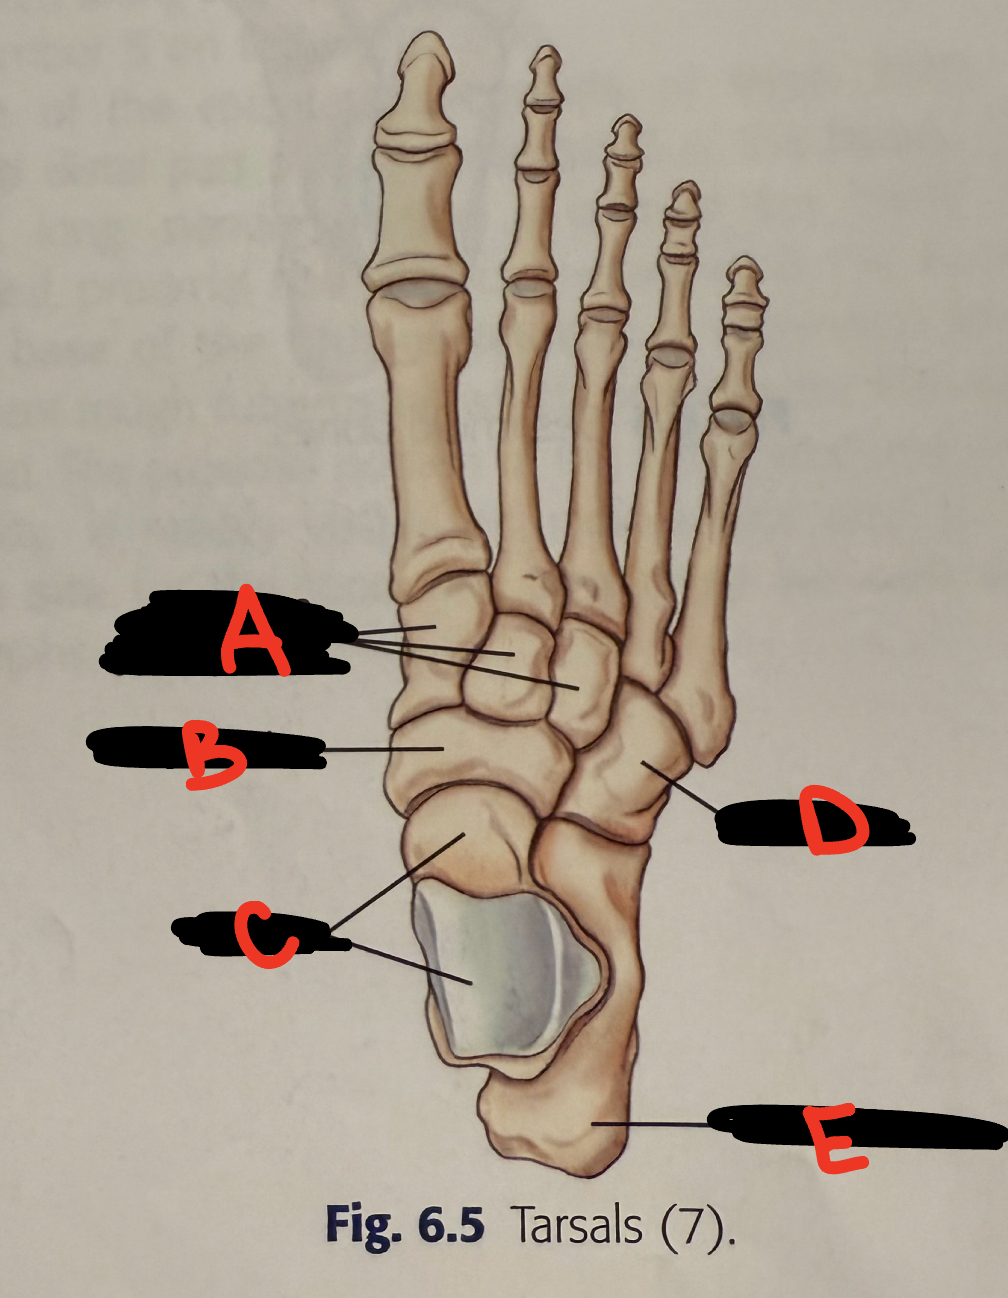

<p>A</p>

A

cuboid

15

New cards

<p>B</p>

B

3rd cuneiform

16

<p>C</p>

C

2nd cuneiform

17

<p>D</p>

D

1st cuneiform

18

<p>E</p>

E

transverse arch